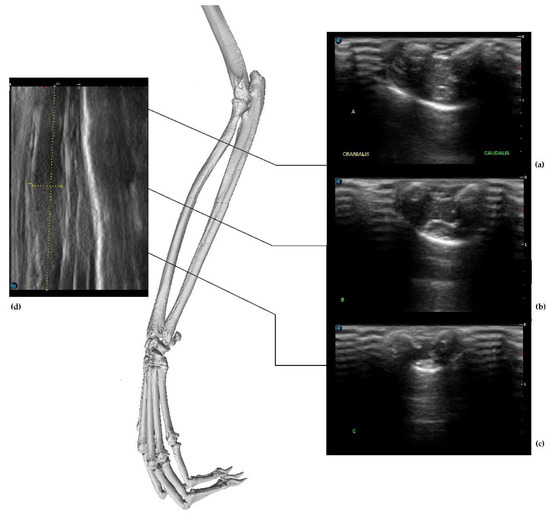

- The radial group included the following muscles: BR, ECRL, and ECRB, which were located at the anterolateral portion of the forearm. US imaging revealed the flat shape and location of the BR muscle belly, which was visible only in a cross-section. The ECRL and ECRB were located at the posterolateral portion of the forearm. They were more cylindrical and elongated. The supinator muscle was not visible in the figure;

- The superficial dorsal group included the EDC and EDM, located at the lateral portion of the forearm;

- The ulnar group was shown with the main visible muscle—the ECU—located at the caudal surface of the forearm from the lateral epicondyle of the humerus. The belly was well visible because of its cylindrical shape. The SDF located at the caudomedial portion of the forearm was the last muscle in this group;

- The deep medial group included the APL, which originated from the interosseous membrane and passed through the wrist as a small tendon. The EPB was not detected. The main mass of the group was represented by the DDF;

- The pronator group included the PT and PQ muscles.